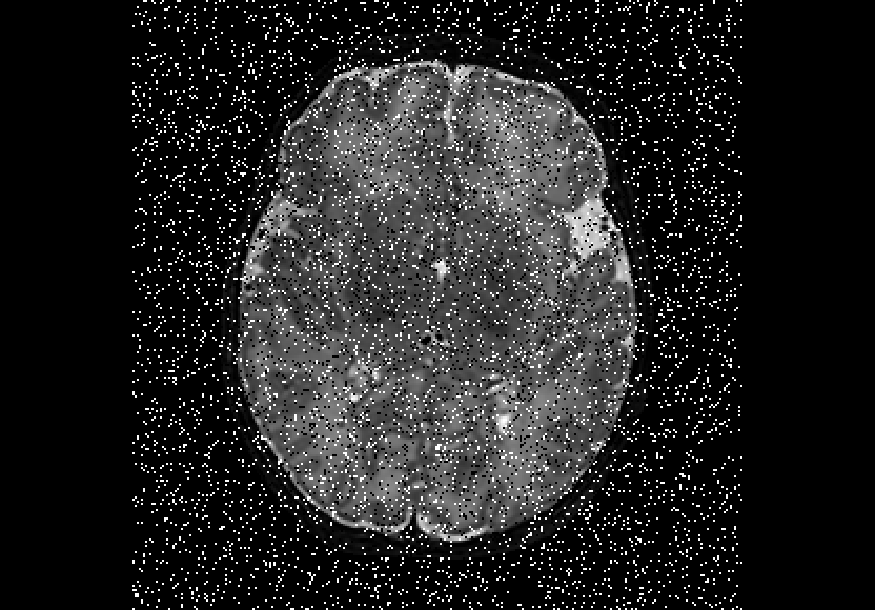

We also explored impulse noise corruptions, such as those introduced by noisy communications channels, faulty memory locations, or damage in channel decoders [6]. The impulse noise generating filter we used in this study is based on the salt-and-pepper (SNP) technique, which randomly generates black and white pixels on the image of interest. The function we used takes into account a parameter called prob, where 0 prob 0.5. A random number is generated for each pixel; if it is less than prob then the function paints the pixel with black, if it is greater than 1-prob then it paints the pixel with white, otherwise the pixel is left unchanged. In other words, the higher the value of prob, the noisier the output can become. We used different values for prob, in particular prob ={0.01, 0.03, 0.05, 0.07, 0.10, 0.15, 0.20}, to create seven different noisy datasets named snp_prob. Examples of axial slices are shown in Figure 4.

Finally, Table 4 shows that the model trained on data injected with different degrees of both Gaussian and salt-and-pepper noise (gaus01, gaus03, gaus04 with = 1, 3, 4 ; snp01, snp05, snp10 with prob = 0.01, 0.05, 0.10) achieves the best overall robustness across the 16 versions of the test set, where even the heaviest filtered images had very few segmentation inaccuracies. For instance, this model demonstrated high levels of robustness on all 10 classes for noise-free data, on data injected with a previously unseen degree of salt-and-pepper noise (e.g. DSCs of 88%-99% on snp20), as well as on data with a previously unseen degree of Gaussian noise (e.g. DSCs of 72%-98% on gaus05). To illustrate, Figure 5 shows examples of the predicted segmentation of the model on the heaviest transformed images of the three filter categories used in these experiments. From the figure it is clear that the model achieved excellent mapping of the brain tissue regions. This shows a tremendous improvement from the baseline model which was trained using a conventional, noise-free approach and thus failed severely on the heavily corrupted images (e.g. DSCs of 0% for all 10 classes on snp20, see Table 2).